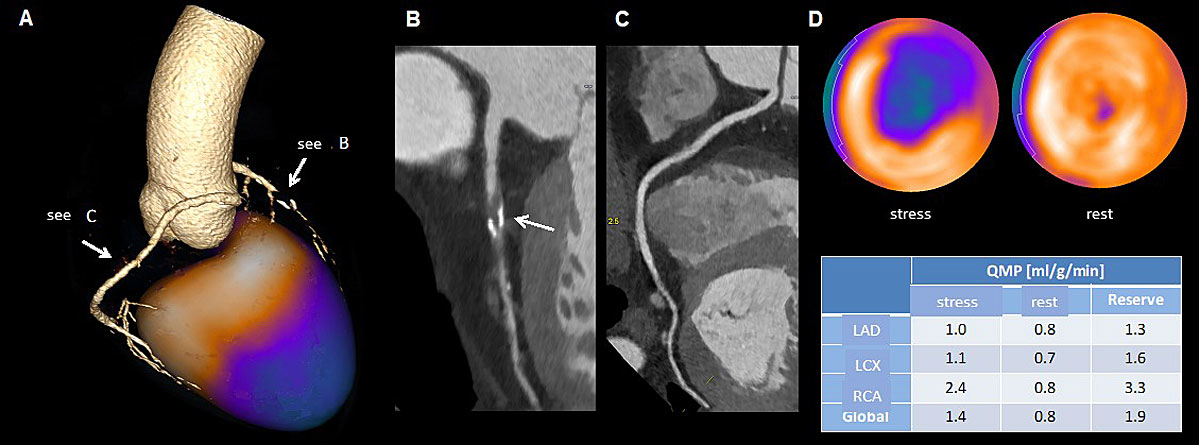

The future outlook for a “one stop-shop” using computed tomography techniques is promising given the complimentary information of CCTA, the functional information of fractional flow reserve, and stress perfusion imaging by CT. We still need to learn how to more effectively incorporate all of the pieces of information gained into the diagnostic and decision-making process (e.g., PET/CT provides information about coronary calcification, coronary artery stenosis, qualitative and quantitative myocardial perfusion, left ventricular function at rest and during stress in less than 45 minutes and with acceptable low radiation exposure); see the example in figure 3. Now that rubidium is available for PET imaging, a cyclotron is no longer necessary to perform cardiac PET because rubidium is a generator-based isotope [65].

Figure 3 Example of hybrid imaging using coronary computed tomographic angiography anatomical and rubidium positron emission tomography perfusion information (a). In (b) and (c), the anatomic information is depicted, demonstrating a high grade left anterior descending artery (LAD) stenosis with non-calcified and calcified parts (b) and demonstrating the right coronary artery (RCA) (c). Figure 3d demonstrates the perfusion defect during stress (ischaemia), the normal perfusion at rest and the decreased flow rates, especially in the LAD territory.